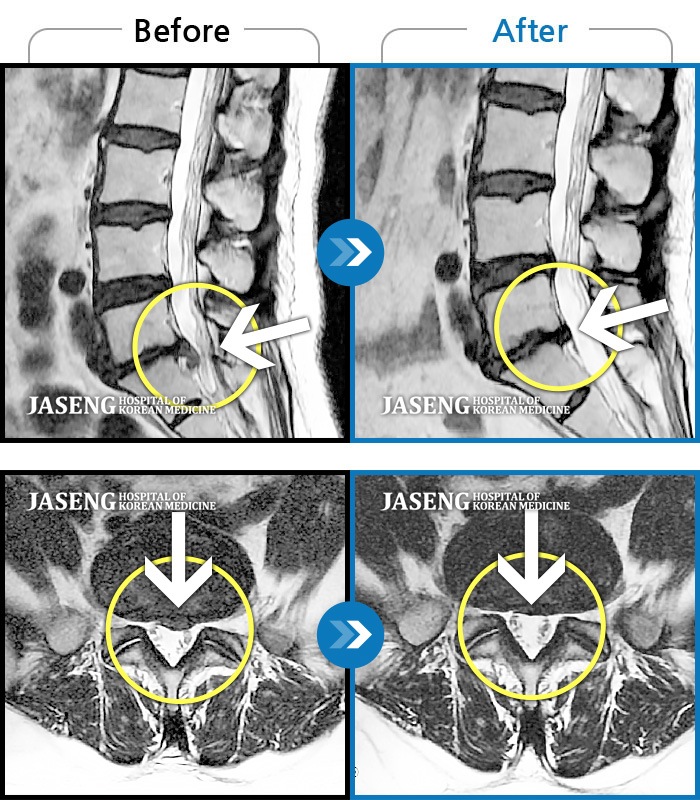

Before

After

환자에게 사전 동의를 받아 동일 조건에서 촬영되었습니다.

개인에 따라 치료 후 부작용이 발생할 수 있으니 의료진과 상담 후 치료를 진행하시기 바랍니다.

움직이지 못할 정도로 허리통증이 심해요.

처음에는 허리만 아프다가 왼쪽 다리가 저리더니 누워있어도 아파져서 자생에서 치료를 받기 시작했어요